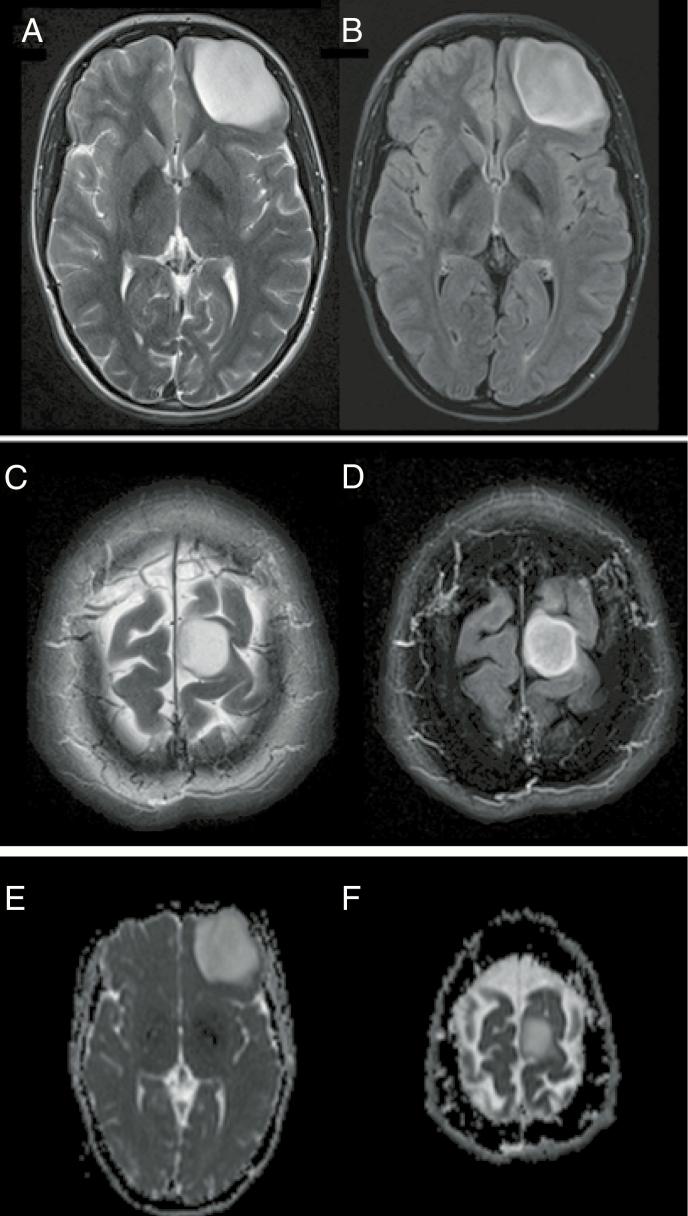

This study aimed to assess the validity and pathophysiology of the T2/FLAIR-mismatch sign for noninvasive identification of isocitrate dehydrogenase (IDH)-mutant 1p/19q non-codeleted glioma.

Magnetic resonance imaging scans from 408 consecutive patients with newly diagnosed glioma (113 lower-grade gliomas and 295 glioblastomas) were evaluated for the presence of T2/FLAIR-mismatch sign by 2 independent reviewers. Sensitivity, specificity, accuracy, positive predictive value (PPV), and negative predictive value (NPV) were calculated to assess the performance of the T2/FLAIR-mismatch sign for identifying IDH-mutant 1p/19q non-codeleted tumors. An exploratory analysis of differences in contrast-enhancing tumor volumes, apparent diffusion coefficient (ADC) values, and relative cerebral blood volume (rCBV) values in IDH-mutant gliomas with versus without the presence of a T2/FLAIR-mismatch sign (as well as analysis of spatial differences within tumors with the presence of a T2/FLAIR-mismatch sign) was performed.

The T2/FLAIR-mismatch sign was present in 12 cases with lower-grade glioma (10.6%), all of them being IDH-mutant 1p/19q non-codeleted tumors (sensitivity = 10.9%, specificity = 100%, PPV = 100%, NPV = 3.0%, accuracy = 13.3%). There was a substantial interrater agreement to identify the T2/FLAIR-mismatch sign (Cohen's kappa = 0.75 [95% CI, 0.57-0.93]). The T2/FLAIR-mismatch sign was not identified in any other molecular subgroup, including IDH-mutant glioblastoma cases ( = 5). IDH-mutant gliomas with a T2/FLAIR-mismatch sign showed significantly higher ADC ( < .0001) and lower rCBV values ( = .0123) as compared to IDH-mutant gliomas without a T2/FLAIR-mismatch sign. Moreover, in IDH-mutant gliomas with T2/FLAIR-mismatch sign the ADC values were significantly lower in the FLAIR-hyperintense rim as compared to the FLAIR-hypointense core of the tumor ( = .0005).

This study confirms the high specificity of the T2/FLAIR-mismatch sign for noninvasive identification of IDH-mutant 1p/19q non-codeleted gliomas; however, sensitivity is low and applicability is limited to lower-grade gliomas. Whether the higher ADC and lower rCBV values in IDH-mutant gliomas with a T2/FLAIR-mismatch sign (as compared to those without) translate into a measurable prognostic effect requires investigation in future studies. Moreover, spatial differences in ADC values between the core and rim of tumors with a T2/FLAIR-mismatch sign potentially reflect specific distinctions in tumor cellularity and microenvironment.

本研究旨在评估T2/液体衰减反转恢复序列(FLAIR)不匹配征对无创识别异柠檬酸脱氢酶(IDH)突变型1p/19q非共缺失型胶质瘤的有效性及病理生理学特征。

由2名独立的评估者对408例新诊断胶质瘤患者(113例低级别胶质瘤和295例胶质母细胞瘤)的磁共振成像扫描进行评估,以确定是否存在T2/FLAIR不匹配征。计算敏感性、特异性、准确性、阳性预测值(PPV)和阴性预测值(NPV),以评估T2/FLAIR不匹配征对识别IDH突变型1p/19q非共缺失型肿瘤的性能。对有和无T2/FLAIR不匹配征的IDH突变型胶质瘤的强化肿瘤体积、表观扩散系数(ADC)值和相对脑血容量(rCBV)值的差异进行探索性分析(以及对存在T2/FLAIR不匹配征的肿瘤内的空间差异进行分析)。

12例低级别胶质瘤(10.6%)存在T2/FLAIR不匹配征,所有这些病例均为IDH突变型1p/19q非共缺失型肿瘤(敏感性=10.9%,特异性=100%,PPV=100%,NPV=3.0%,准确性=13.3%)。在识别T2/FLAIR不匹配征方面,评估者间有高度一致性(Cohen's kappa=0.75[95%CI,0.57-0.93])。在任何其他分子亚组中均未发现T2/FLAIR不匹配征,包括IDH突变型胶质母细胞瘤病例(n=5)。与无T2/FLAIR不匹配征的IDH突变型胶质瘤相比,有T2/FLAIR不匹配征的IDH突变型胶质瘤显示出显著更高的ADC值(P<0.0001)和更低的rCBV值(P=0.0123)。此外,在有T2/FLAIR不匹配征的IDH突变型胶质瘤中,与肿瘤的FLAIR低信号核心相比,FLAIR高信号边缘的ADC值显著更低(P=0.0005)。

本研究证实了T2/FLAIR不匹配征对无创识别IDH突变型1p/19q非共缺失型胶质瘤具有高特异性;然而,敏感性较低且适用性仅限于低级别胶质瘤。与无T2/FLAIR不匹配征的IDH突变型胶质瘤相比,有T2/FLAIR不匹配征的IDH突变型胶质瘤中更高的ADC值和更低的rCBV值是否转化为可测量的预后效应,需要在未来的研究中进行探究。此外,有T2/FLAIR不匹配征的肿瘤核心与边缘之间ADC值的空间差异可能反映了肿瘤细胞密度和微环境的特定差异。